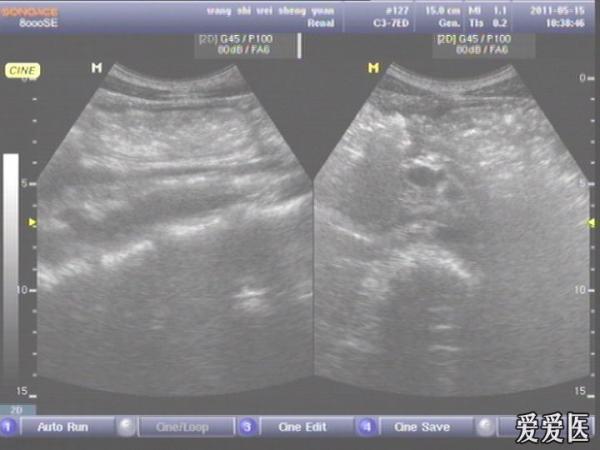

患者,男,38岁,进食后突发上腹部持续性剧烈疼痛一小时来查。超声见横膈与肝之间、上腹部皮下气体强反射回声,后伴多重反射,肝前、肝肾间隙,腹腔肠管间均可见游离无回声区。直视腹部见上腹部似板样。结合病史提示“胃肠道穿孔”。急诊手术证实。